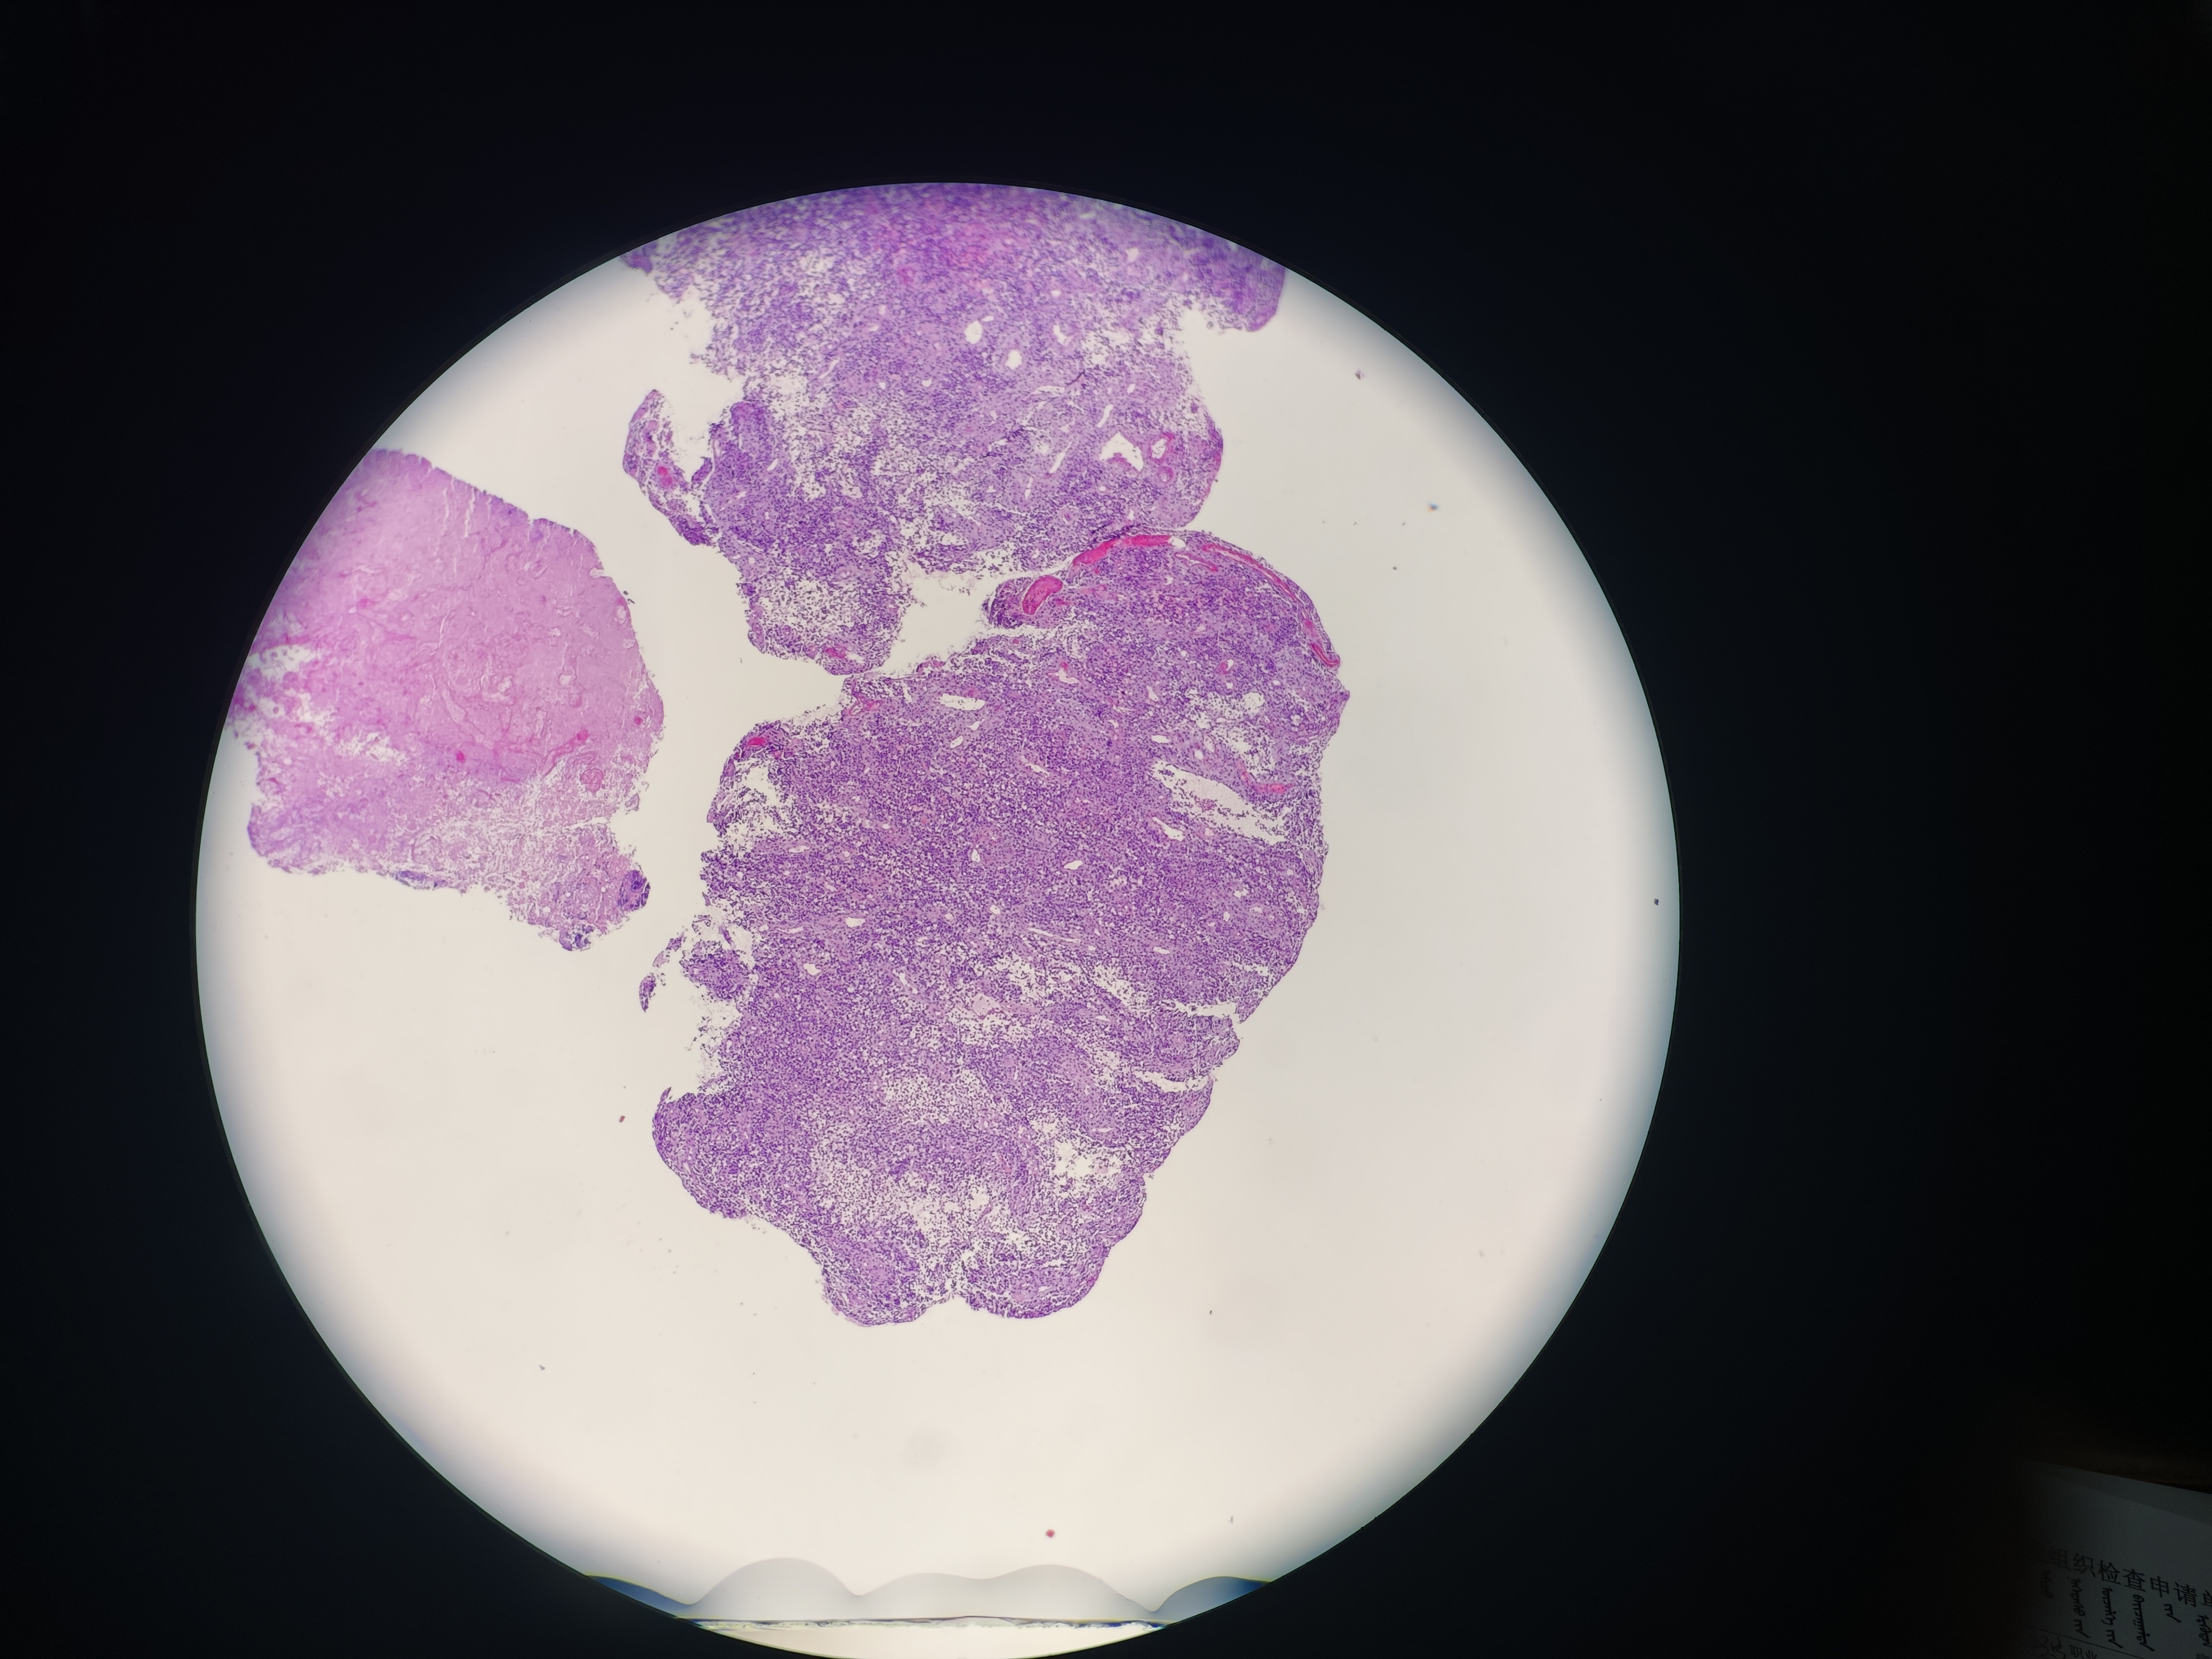

食管癌

食管距门齿33~38cm处可见环管腔半周隆起性病变,表面破溃,易出血,活检6块,质脆

食管活检

灰白软组织6块,直径0.1~0.2cm

请教老师,这个报什么癌?

图4